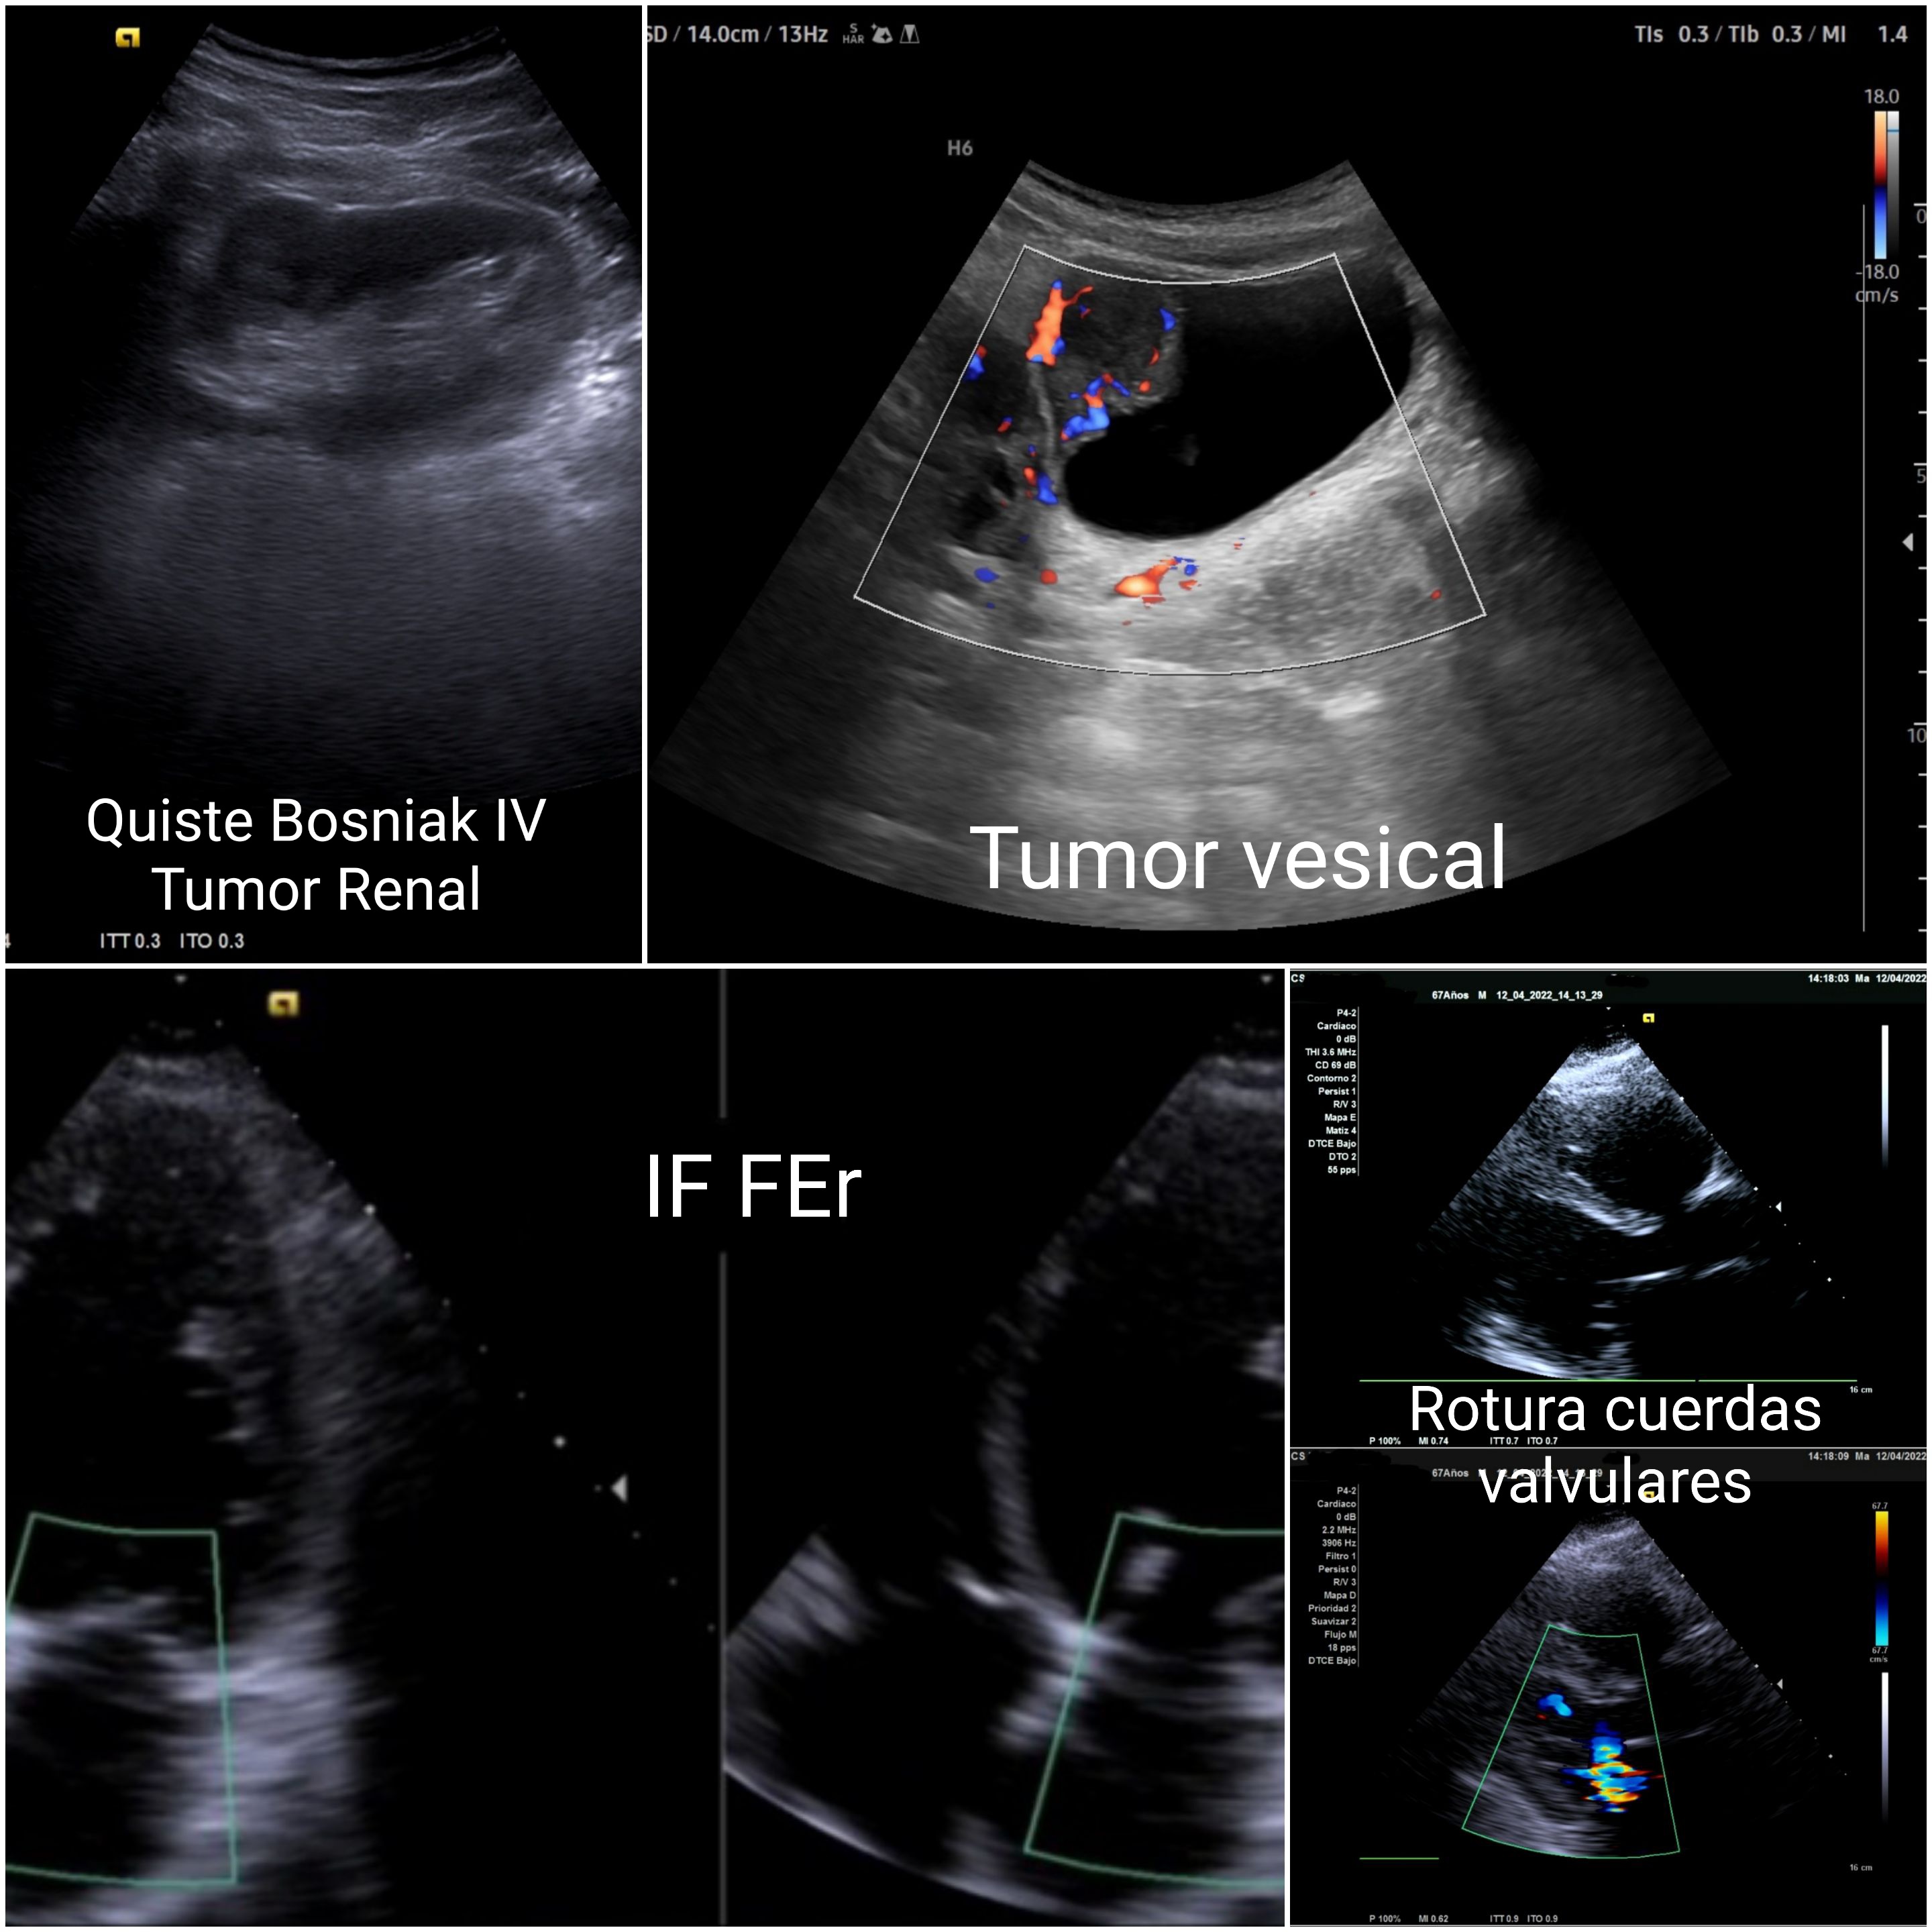

Se presentan 12–15 casos ilustrativos: (1) rotura de cuerdas mitrales recuperada desde lista de espera (ecocardioscopia); (2) postcirugía cardíaca dado de alta con derrame y congestión no detectados; (3) insuficiencia cardíaca (IC) tras pancreatitis con derrame pleural; (4) IC dada de alta pendiente de ecocardiografía, en AP se confirma FE reducida; (5) Trombosis venosa (TV) con disnea sin sin angio-TC; (6) ELA: fasciculaciones por ecografía con alta demora para neurología; (7) desprendimiento de retina reenviado dos veces a urgencias Hospital; (8) aumento del diámetro de la vaina del nervio óptico con sospecha de patología de nervio óptico; (9) lesión de Hill-Sachs no detectada en hospital; (10) lesión renal Bosniak IV (carcinoma renal); (11) tumor vesical de pared tras ecografía hospitalaria previa normal; (12) angioleiomioma etiquetado como quiste epidérmico.